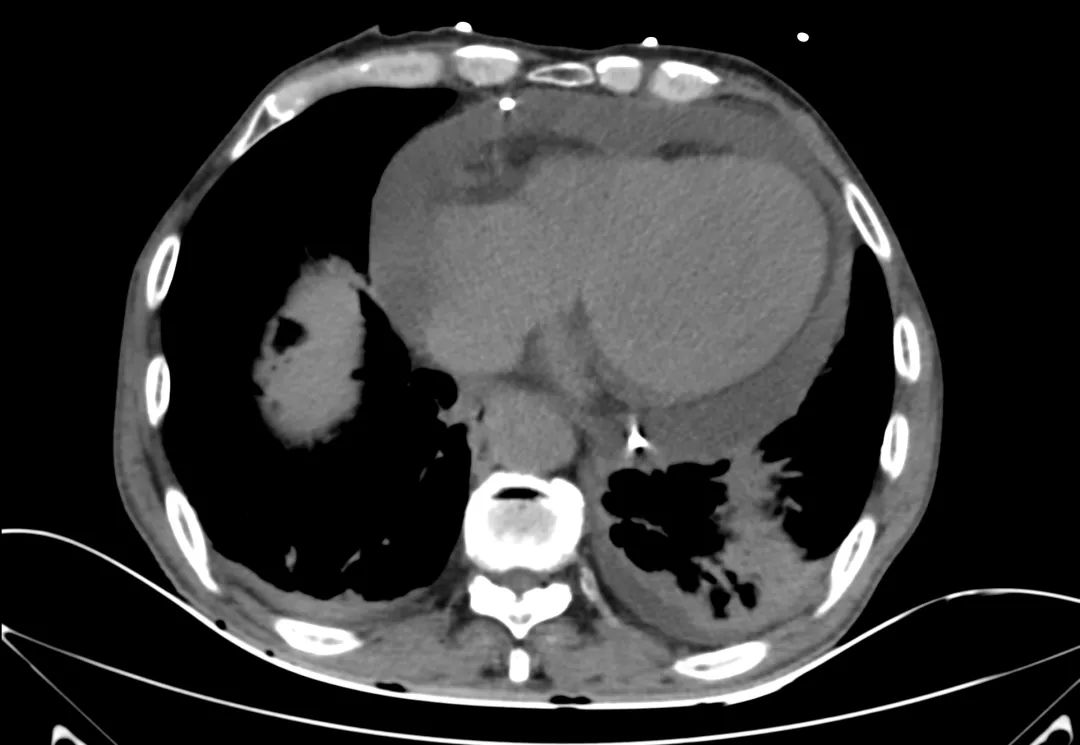

胸部CT

主动脉根部CT断层

根部角度/瓣环/左室流出道

左冠风险评估